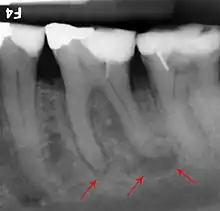

If disease is identified through this process, then a full periodontal analysis is performed, often by dental hygienists, oral health therapists, or specialist periodontists. This involves full mouth periodontal probing and taking measurements of pocket depths, clinical attachment loss and recession. Along with this other relevant parameters such as plaque, bleeding, furcation involvement and mobility are measured to gain an overall understanding of the level of disease. Radiographs may also be performed to assess alveolar bone levels and levels of destruction.[40]

In periodontal health, the alveolar bone surrounds the teeth and forms the bony socket that supports each tooth. The buccal and lingual plates and lining of the sockets are composed of thin, yet dense compact or cortical bone.[3] Within the cortical plates and dental sockets lies cancellous bone, a spongy or trabecular-type bone which is less dense than compact bone.[6] The anatomic landmarks of the alveolar process includes the lamina dura, the alveolar crest, and the periodontal ligament space.[9]

Periodontal disease encompasses a number of diseases of the periodontal tissues that result in attachment loss and destruction of alveolar bone.[11]